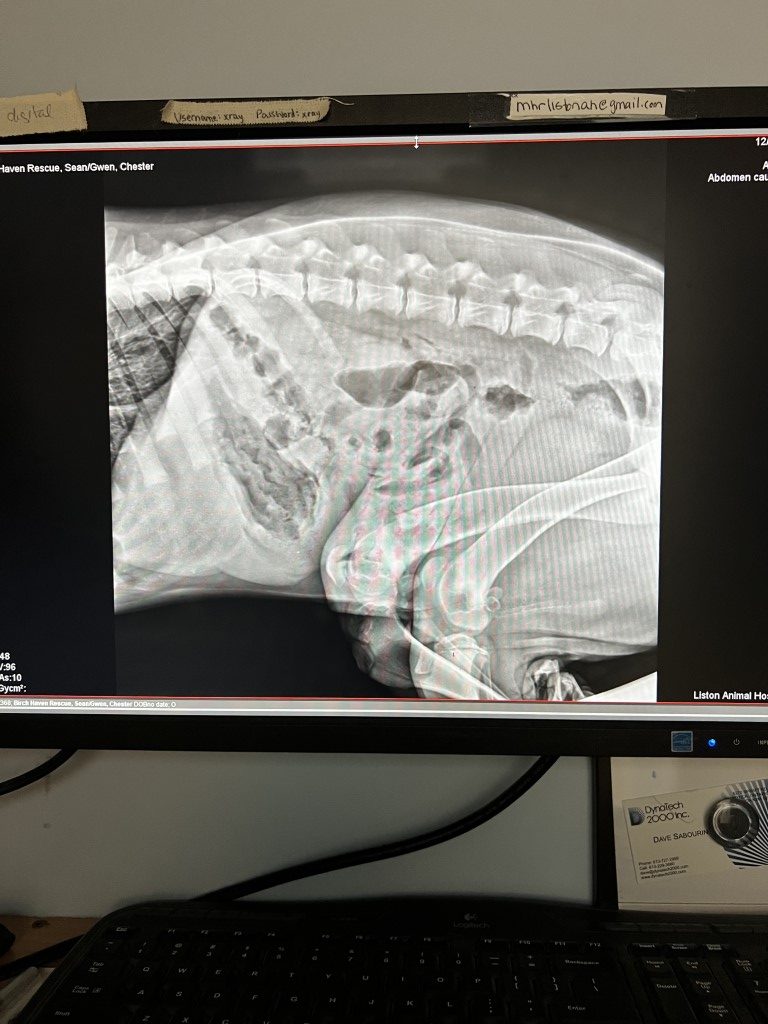

Chester’s x-ray